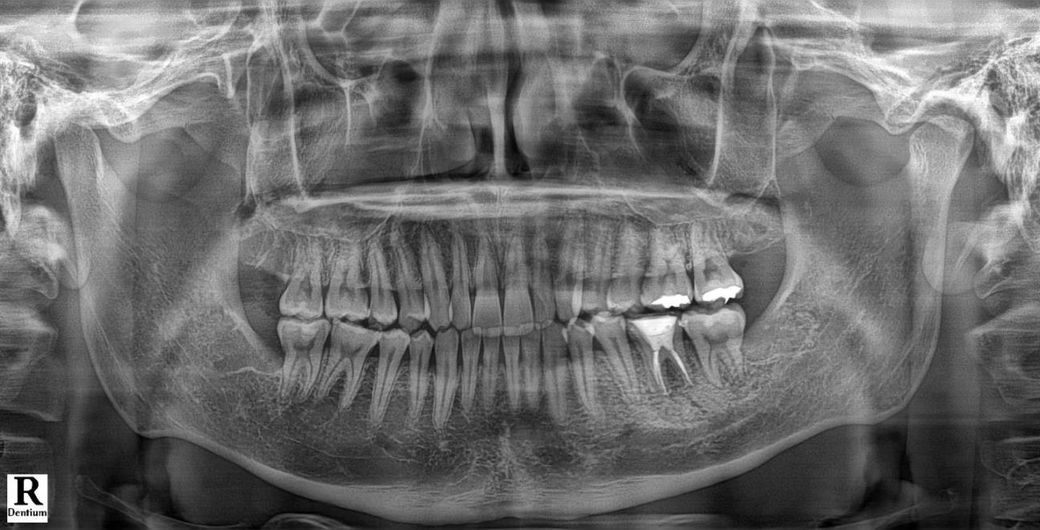

첫번째 사진은 사랑니 발치전(06.11)에 찍은 파노라마 사진입니다.

Q1. 두번째 사진에서 보면 신경치료 한 치아(오른쪽 하단 어금니) 왼쪽 뿌리쪽에 신경치료한 약재가 두갈래로 갈라져있습니다.

반면 첫번째 사진에서는 파노라마상 약재가 갈라져있는게 보이지 않는데 무슨 문제가 생긴 것인가요?

Q2. 2번째 사진에서 신경치료 받은치아 오른쪽 치아 인대쪽에서 검은색 염증같이 무언가 보입니다. 염증일까요?

엑스레이 촬영에 따라서 근관 2개가 겹쳐 보이는경우가 잇고 나눠져 보이는 경우 인거 같습니다.

뿌리 끝에 있는 재료의 형태는 사진을 찍는 각도에 따라 다르게 보이기도 합니다.

1. 약재가 아니고 gp cone이라는 충전재이며 어금니는 신경관이 근심에 2개, 원심에 1~2개 있습니다 근심 2개의 신경관이 첫번째 엑스레이에서는 중첩되어 있고, 두번째 사진에선 각도가 잘 나와서 2개다 보이는 겁니다

2. 원심쪽 뿌리에 염증 양상이 있어보이긴 합니다